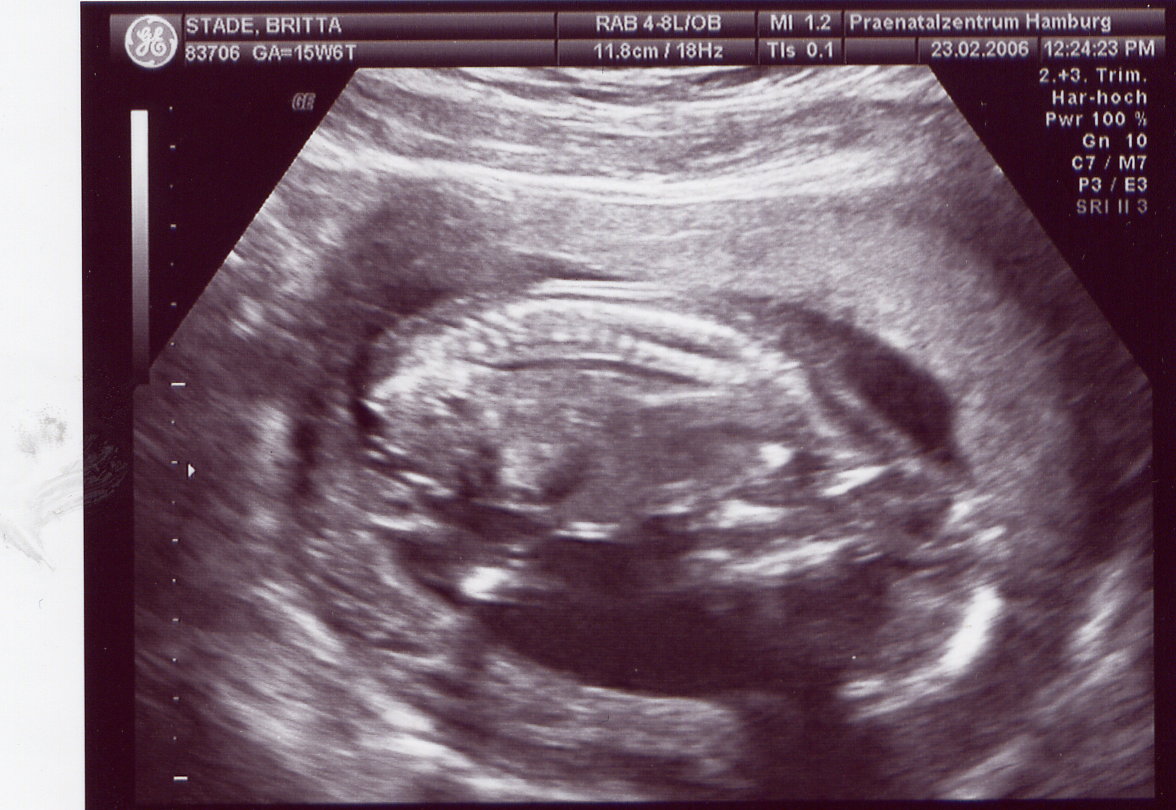

Das Organscreening wird wiederum aufgrund meines Alters gemacht und weil ich durch künstliche Befruchtung schwanger geworden bin. Mein Arzt geht da lieber auf Nr. sicher. Ihr wißt doch, daß einem nur noch 3 US-Bilder zur Verfügung stehen und ich hab doch schon 5, zwei davon wurden mir geschenkt

Aber leider sind die US-Bilder von meinem Haus-Gyn so dunkel, daß diese ganz schlecht zu scannen sind, wie ihr vielleicht schon gesehen habt. Habt ihr sonst einen Tip?